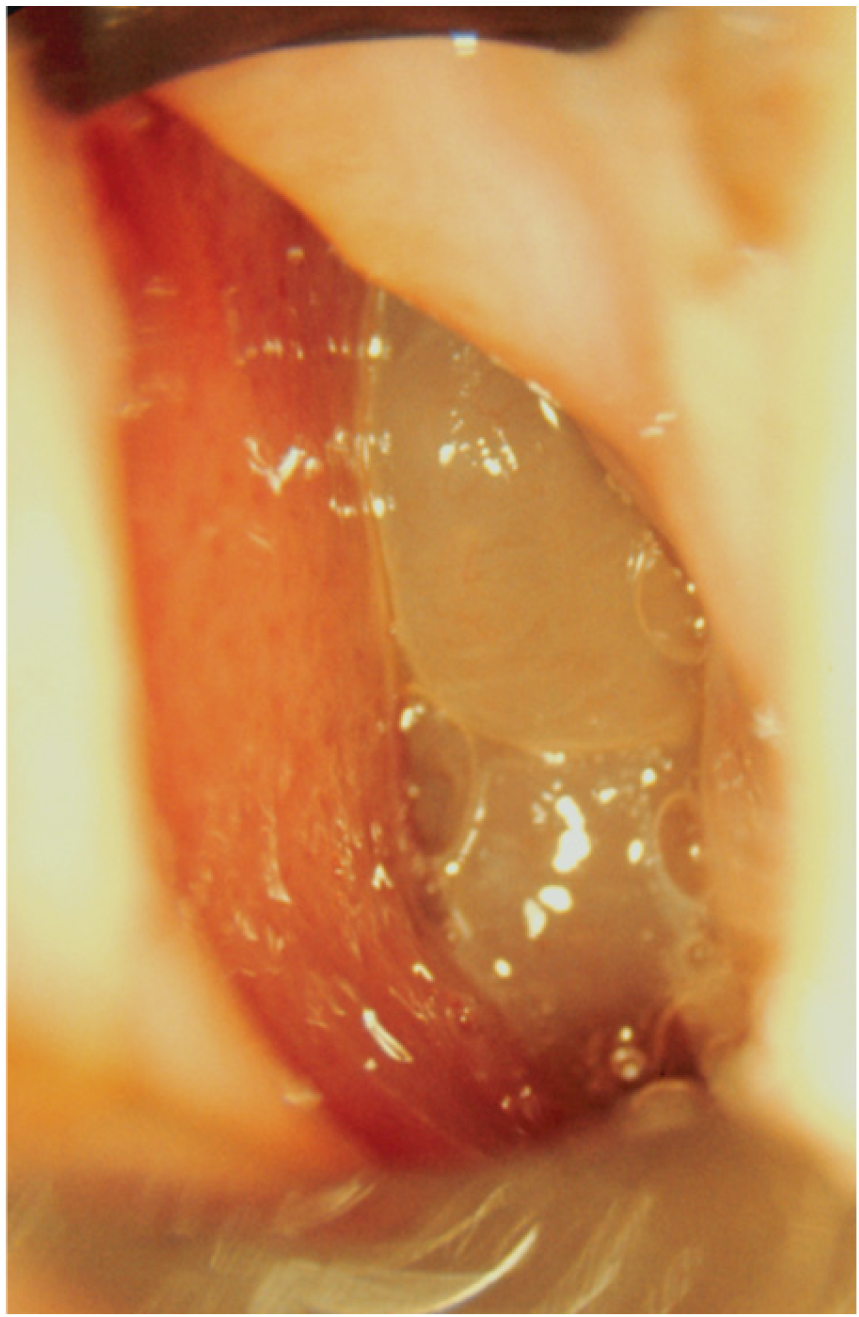

- 0 = no polyps;

- 1 = polyps confined to the middle meatus;

- 2 = multiple polyps occupying the middle meatus;

- 3 = polyps extending beyond the middle meatus;

- 4 = polyps completely obstructing the nasal cavity.

- 1 = small polyps in the middle meatus not reaching the inferior border of the middle meatus;

- 2 = nasal polyps reaching below the lower border of the middle meatus;

- 3 = large polyps reaching the lower border of the inferior turbinate or polyps medial to the middle turbinate;

- 4 = large nasal polyps causing complete obstruction of the inferior nasal cavity.

- Djupesland, P.; Reitsma, S.; Hopkins, C.; Sedaghat, A.; Peters, A.; Fokkens, W.J. Endoscopic grading systems for nasal polyps: Are we comparing apples to oranges? Rhinology 2022, 60, 169–176. [Google Scholar] [CrossRef] [PubMed]

- Gevaert, P.; Gevaert, P.; De Craemer, J.; De Craemer, J.; Bachert, C.; Bachert, C.; Blauwblomme, M.; Blauwblomme, M.; Chaker, A.; Chaker, A.; et al. European Academy of Allergy and Clinical Immunology position paper on endoscopic scoring of nasal polyposis. Allergy 2023, 78, 912–922. [Google Scholar] [CrossRef] [PubMed]